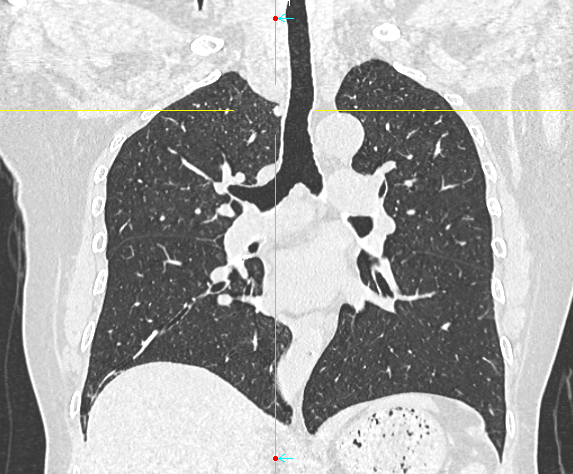

数月前,66岁的龚女士在肺癌术后随访复查中,胸部CT报告显示其右上肺新发实性结节一枚,并由刚开始发现时的5mm逐步增大至10mm。更棘手的是,这个结节位于右肺上叶尖段的纵隔胸膜下,位置极其刁钻。面对这份报告,患者龚女士陷入了深深的焦虑。因为其7年前因右中肺肿瘤行右中肺癌根治术,对于新发的实性结节为何种性质,是新发肺恶性肿瘤或是良性病变,亦或是原肺癌复发转移,目前均不能明确。辗转多家医院,得到的建议多为定期观察,等待变化或考虑创伤较大的传统穿刺活检,但结节位置非常深,单纯CT引导下定位穿刺很难精准到达,且需穿行的肺组织较多,创伤较大。

胸外科马海涛主任团队对龚女士的病情进行了深入细致的评估:结节虽小,但形态学特征具有风险,且结节逐步增大,结合既往肺癌病史,考虑肿瘤复发可能,“定期观察”方案会让患者持续承受心理煎熬。然而,传统的CT引导下经皮肺穿刺定位,对于如此深部、微小的结节,极易导致气胸、出血等并发症,风险极高。

马主任解释系统原理:“这套系统就像为我们医生的操作装上了‘肺部GPS’。它通过术前将患者的CT影像数据导入系统,构建出独一无二的肺部三维地图。术中,在磁场的引导下,我们操控一根细如发丝的导航探头,经由患者的口腔、气管这一自然通道,毫无创伤地直达常规支气管镜无法到达的肺外周深处,精准地停靠在目标结节旁边。磁导航支气管镜的优势是决定性的。它实现了‘经自然腔道、无创抵达’,彻底避免了经皮穿刺可能引起的高达20%-30%的气胸风险,为定位深部结节提供了安全、精准的解决方案。